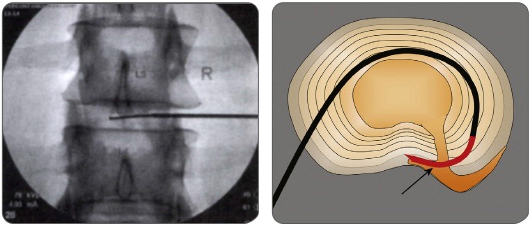

플라즈마(고주파)수핵성형술

고주파 에너지를 이용하여 플라즈마를 형성하고, 이 플라즈마에 의해 통증을 유발하는 분자 구조를 분해하여 제거하는 기능과 연조직이나 수핵을 응고수축 시키는 기능의 2가지 작용기전을 이용하여 돌출된 수핵을 감압하게 됩니다.

치료과정

치료 시간은 20분 내외가 소요됩니다.

복와위 자세에서 국소마취를 시행합니다.

X-ray 가이드로 카테터를 디스크내로 삽입합니다.

카테터를 통해 고주파를 전달하게되고, 카테터를 제거합니다.